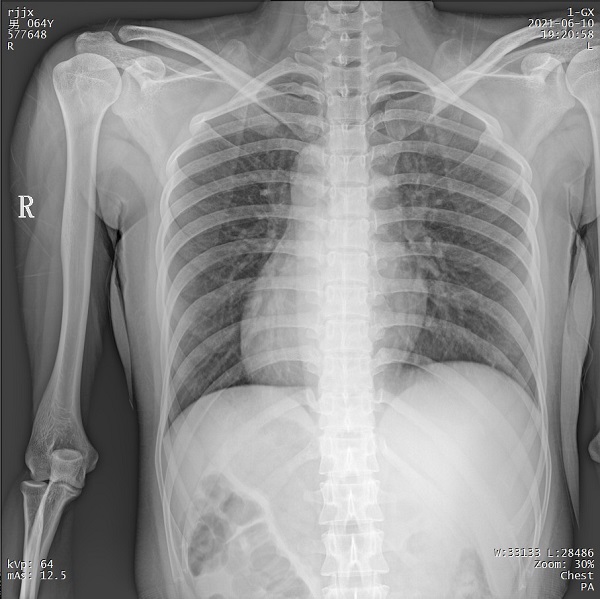

二、1ms 短时曝光 定格心肺运动瞬间影像

PLX5500能够在最短1ms的曝光时间内输出足量的X射线,获取清晰图像。特别适用于拍摄肺炎、尘肺病、肺结核等难以憋气的患者,避免了因患者肺部呼吸运动而产生的运动伪影的影响,瞬间定格清晰图像,以供医生精确诊断。